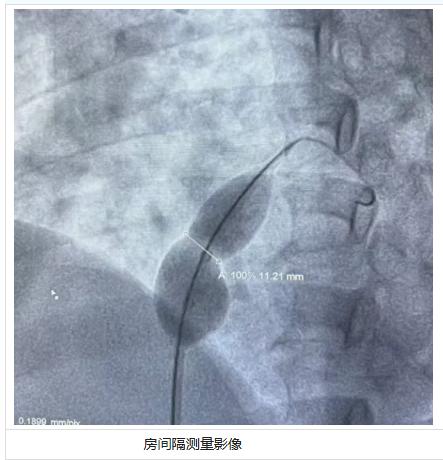

手术中,团队严格遵循标准化介入流程:首先经患者右股静脉穿刺置入穿刺鞘,沿导丝将 ConSiz® 导管精准送入房间隔缺损的远端小孔;随后在 TEE 实时监测下,缓慢注入 1∶4 配比的碘海醇与生理盐水混合造影剂,使球囊逐步膨胀。随着球囊充盈,影像画面中清晰呈现出缺损口的 “腰部” 形变,以及分流完全消失的关键瞬间 —— 术者即时记录下缺损的伸展直径为 11.21mm,并据此迅速确定了最优封堵器型号,顺利完成缺损封堵操作。

房间隔测量影像术后超声与影像检查显示,封堵器位置精准、固定牢固,患者房间隔缺损处无残余分流,肺动脉压力较术前明显改善,手术取得圆满成功。目前患者恢复良好,已顺利出院。